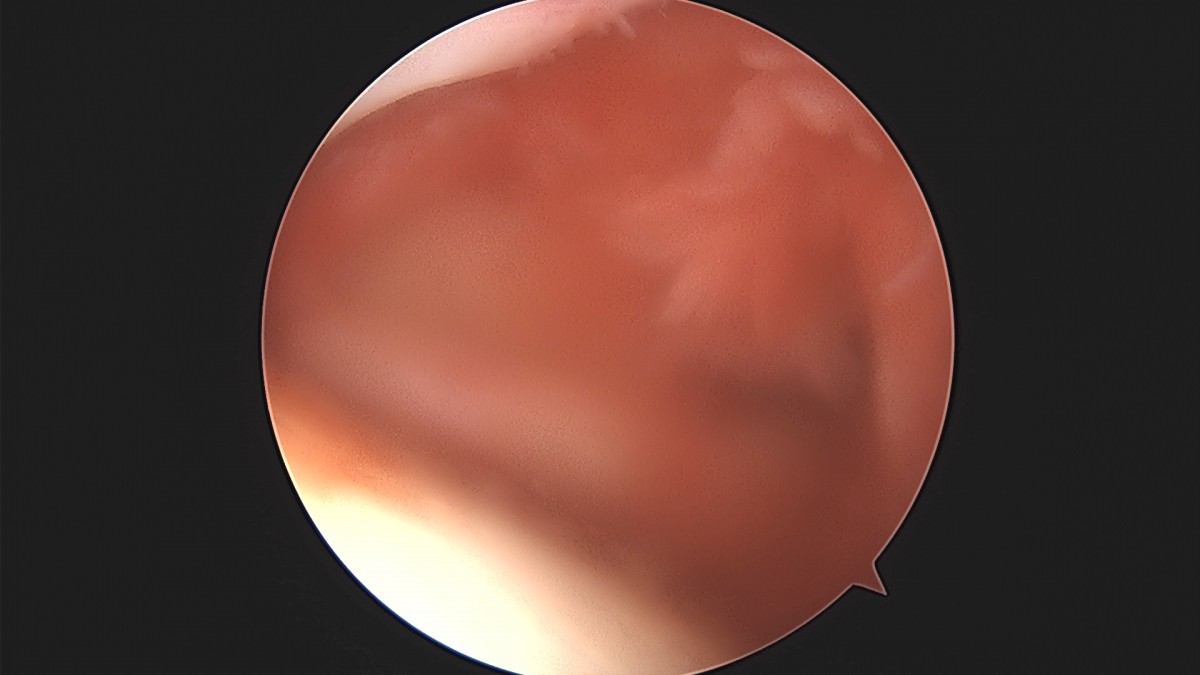

이재상원장님 어깨 견봉하 감압술 및 관절낭 이완술 박창O 환자

dae765e4d9ac96aee867c9d6292d8784_1758004610_4344.jpg

dae765e4d9ac96aee867c9d6292d8784_1758004611_0512.jpg

dae765e4d9ac96aee867c9d6292d8784_1758004611_6449.jpg

dae765e4d9ac96aee867c9d6292d8784_1758004612_2234.jpg

dae765e4d9ac96aee867c9d6292d8784_1758004612_8006.jpg

dae765e4d9ac96aee867c9d6292d8784_1758004613_387.jpg

dae765e4d9ac96aee867c9d6292d8784_1758004613_9706.jpg

dae765e4d9ac96aee867c9d6292d8784_1758004614_5462.jpg

dae765e4d9ac96aee867c9d6292d8784_1758004615_1271.jpg

dae765e4d9ac96aee867c9d6292d8784_1758004615_7368.jpg